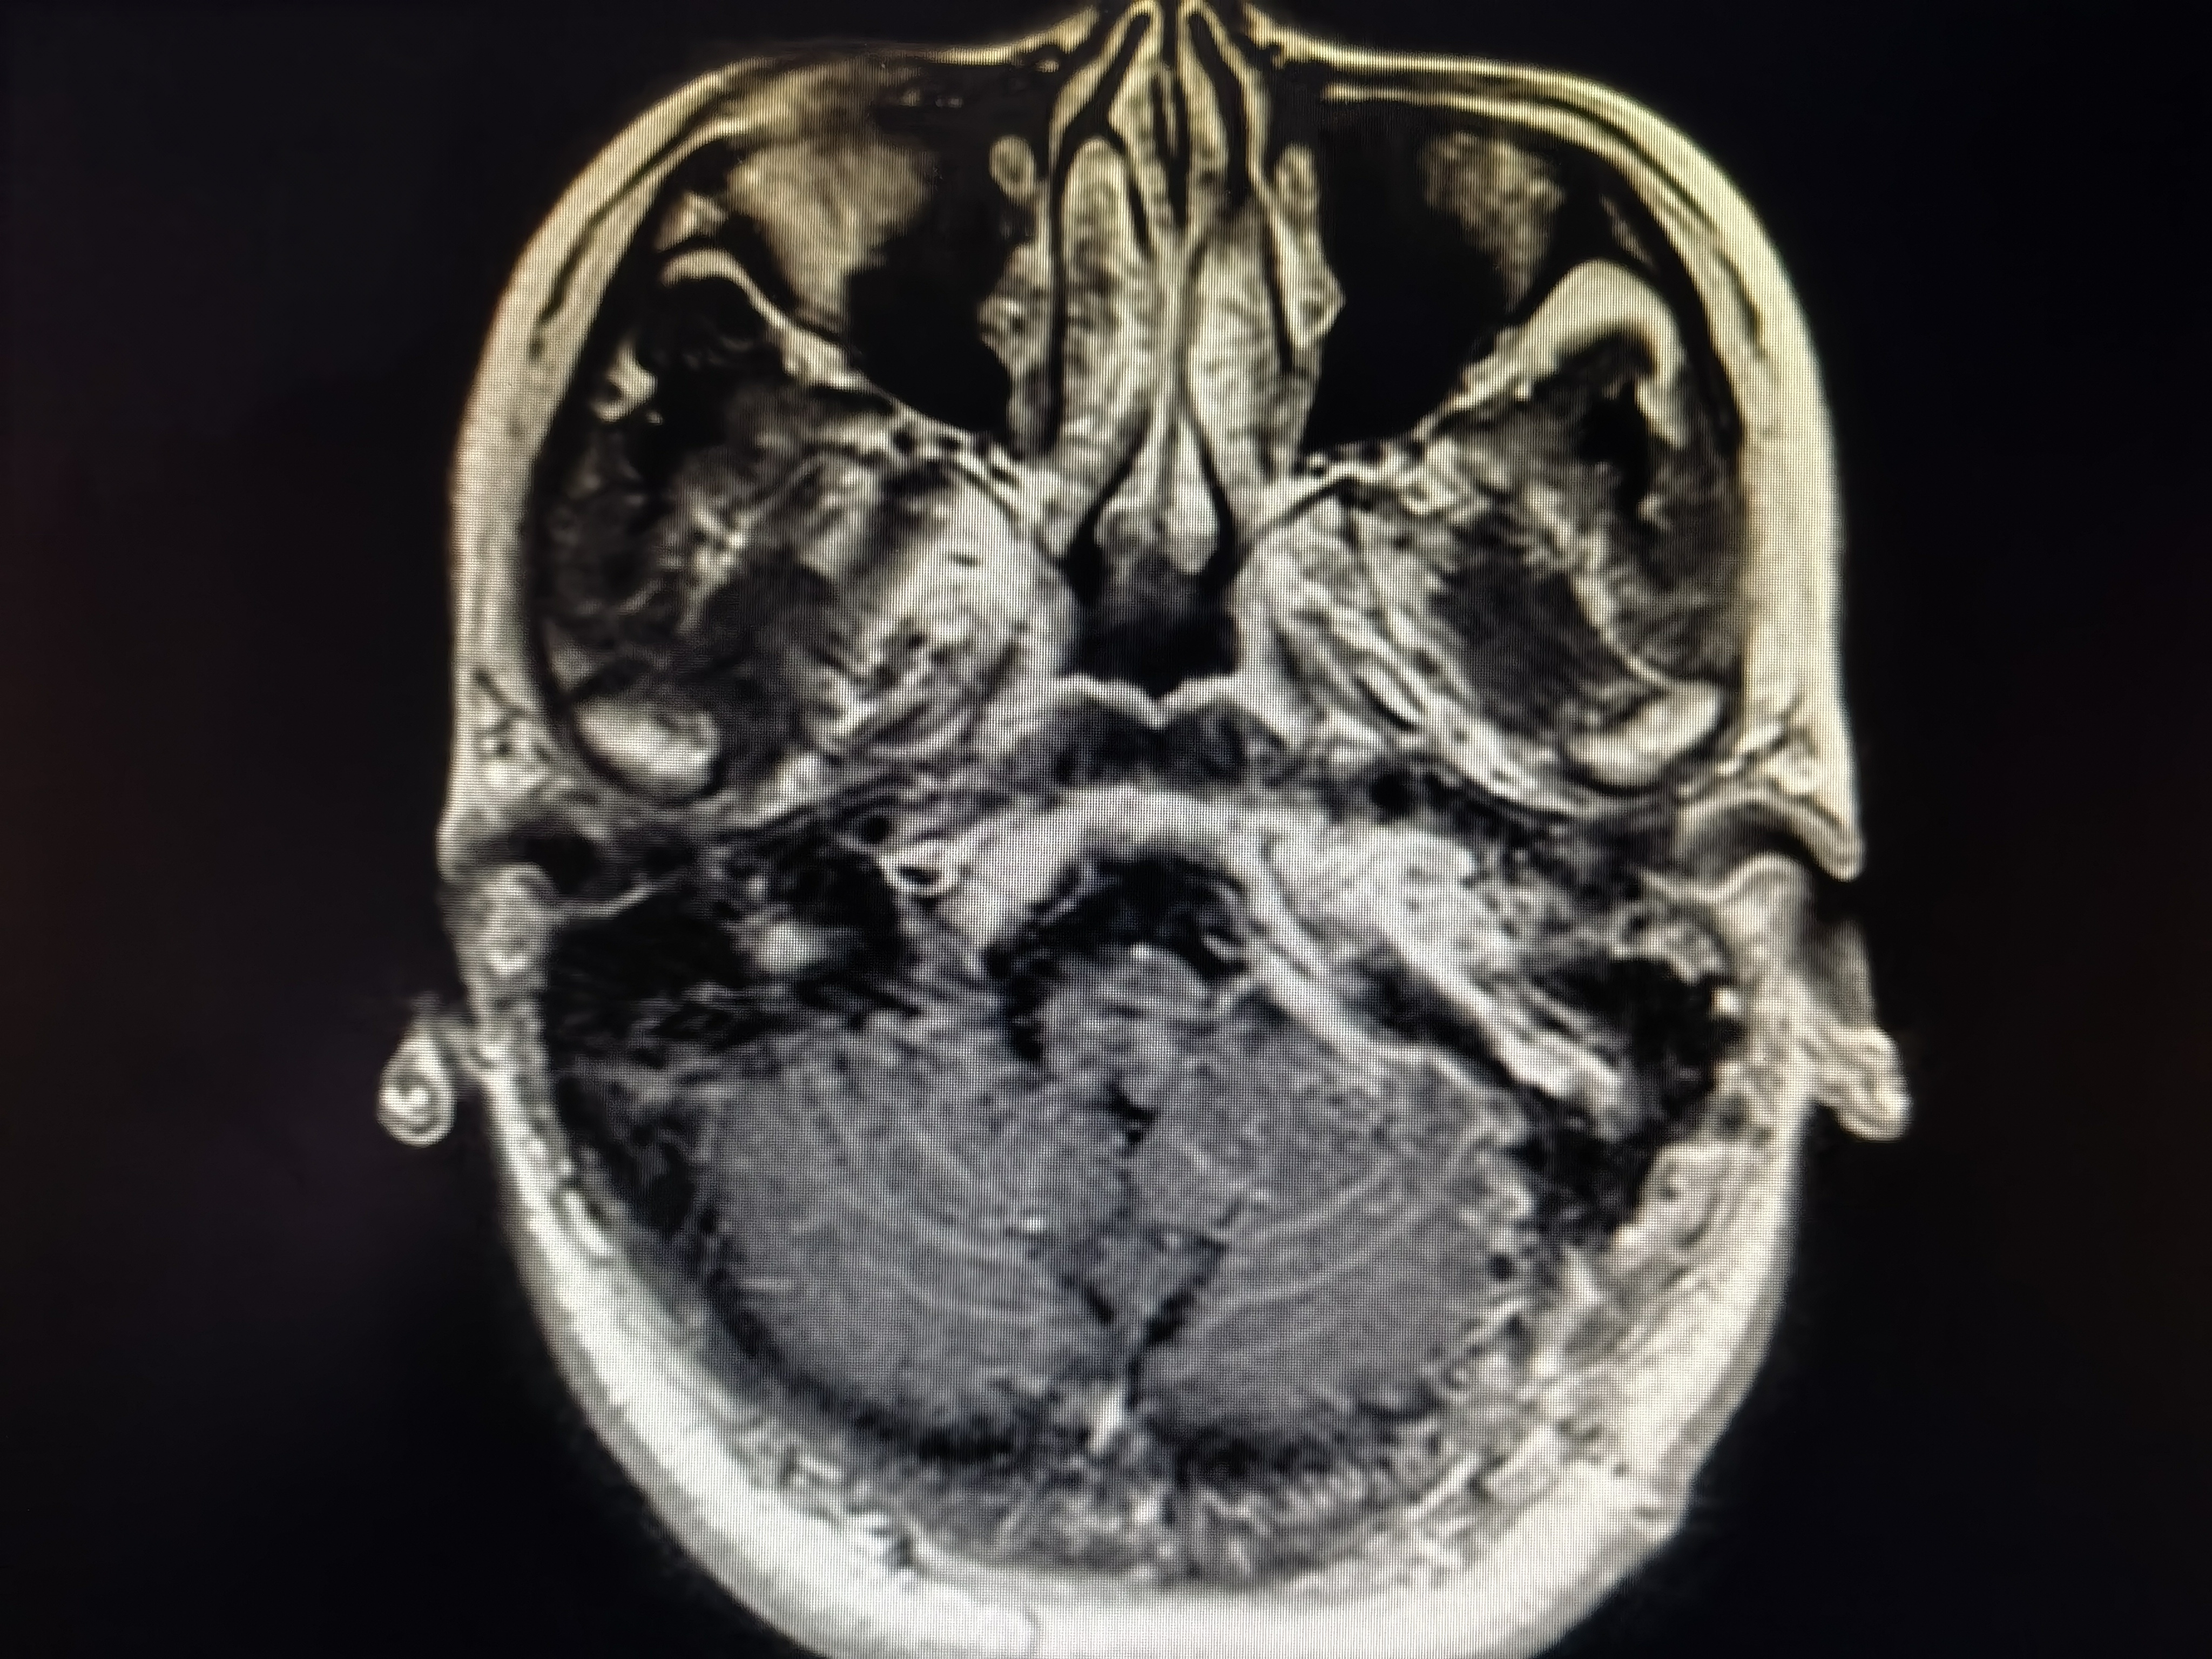

术前磁共振